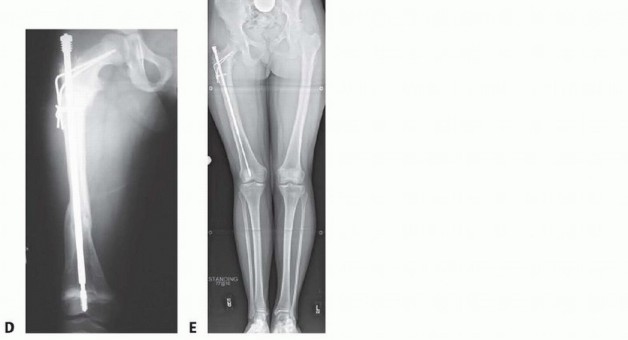

FIG 3 • A,B. Plating of the proximal femur in a young child with progressive bowing pain and recurrent fractures at the end of the plate. C. An 8-year-old child treated with an adult nail with lateral migration distally, coxa vara, and proximal growth inhibition. D. The same child treated with the Fassier-Duval nail and valgus osteotomy 6 months postoperatively. E. Follow-up near maturity demonstrating telescoping of the nail, maintenance of the valgus neck-shaft angle but residual leg length discrepancy related to initial surgery.

Plating predictably leads to stress reaction, progressive deformity, and fracture (FIG 3A,B). Use relatively small, flexible nails to share stress.

Excessively rigid nails may lead to disappearing bone (FIG 3C,D). Do not remove nails electively.

## TECH FIG 4 • A. A 2½ year-old boy with OI who developed progressive painful right coxa vara with walking.

B. Age 3 developing coxa vara on left with progression in right hip. C. Age 3 bilateral valgus osteotomies. Note valgus correction and alignment of lateral cortex of the proximal segment with right femoral shaft. D. Distal femoral osteotomy to correct associated diaphyseal varus. E. At 13-month follow-up, maintenance of correction is demonstrated. The femoral head is growing away from the wires, and varus may recur.